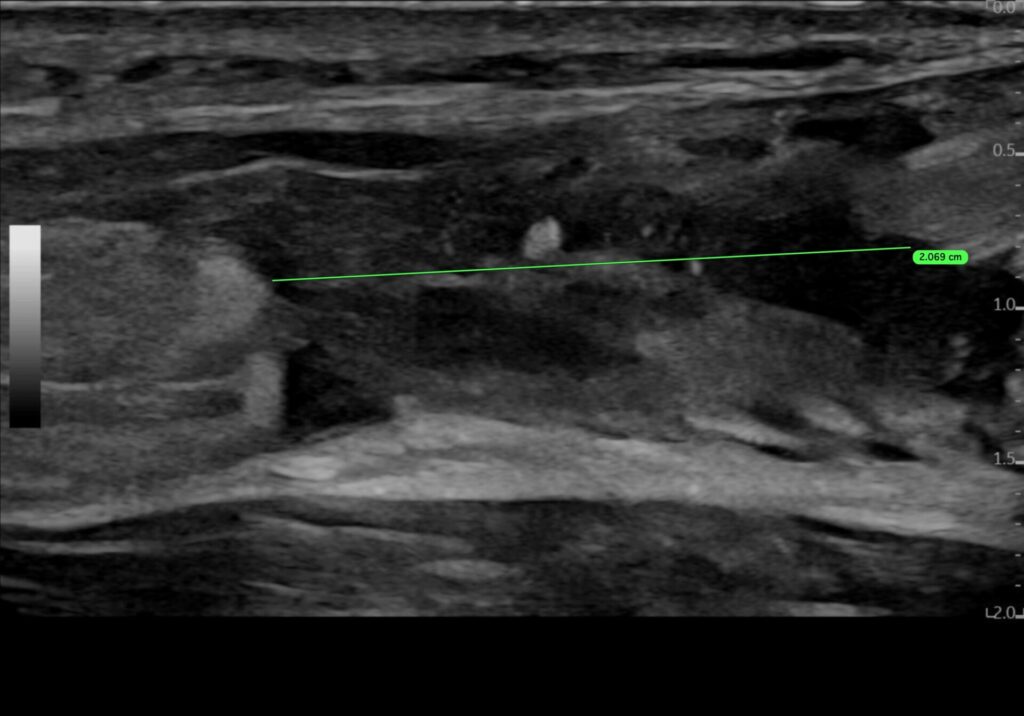

3. Diastase der Sehnenstümpfe

- Beurteilung in Neutralstellung

- Beurteilung in maximaler Plantarflexion

- Restadaptation vollständig? ☐ ja ☐ nein

Die Achillessehne zeigt eine Kontinuitätsunterbrechung im Bereich der mid-portion / des muskulotendinösen Übergangs / insertional. Die Sehnenenden erscheinen glatt / fransig und gegebenenfalls retrahiert. In Neutralstellung besteht eine Diastase der Sehnenstümpfe. In Plantarflexion zeigt sich eine Annäherung der Sehnenenden mit vollständiger / unvollständiger Adaptation.